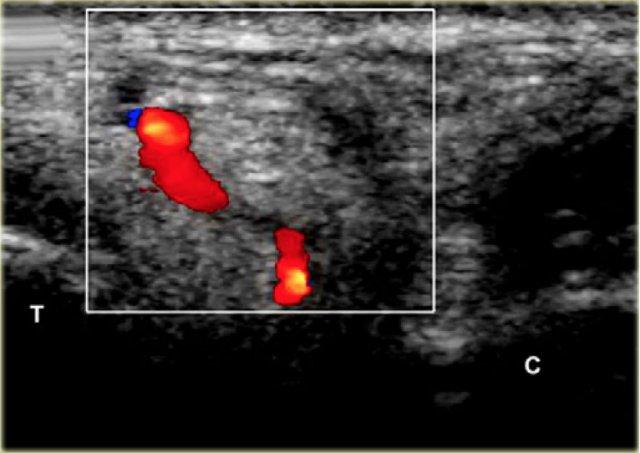

Đầu kim (mũi tên) được nhìn thấy trong xoang cổ chân hình nón, được giới hạn bởi xương sên (T) và xương gót (C).

Tùy thuộc vào mức độ viêm, có thể có hiện tượng xung huyết trong khoang và có thể thấy các mạch máu xen kẽ, những mạch máu này cần được tránh. Điều này tương đối dễ dàng, đặc biệt khi sử dụng doppler màu